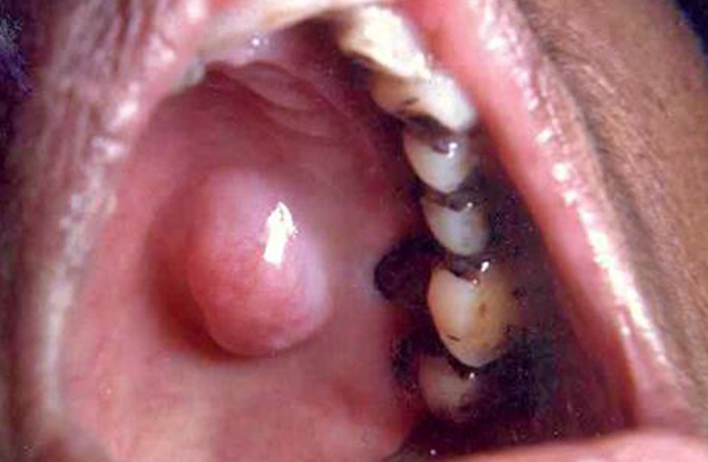

上颚,即我们口腔的“顶部天花板”,这个特殊部位一旦发生肿瘤,其最凶险之处在于极易向颈部淋巴结转移。患者吴女士便深受其扰,术后不到一年,肿瘤复发的信号——左侧下颌可触及的肿大包块便再次出现,这意味着病情已进展至淋巴结转移阶段,她也因此来到我院,寻求力挽狂澜的治疗良机。

据悉,吴女士在其他医院就诊后肿瘤复发,左上腭出现肿块,双侧颈部淋巴结转移的复杂局面,这标志着病情已进入更具挑战性的阶段。初始手术的局限性与后续治疗的缺失,导致肿瘤卷土重来,这无疑对诊疗团队的技术与策略提出了极高要求。